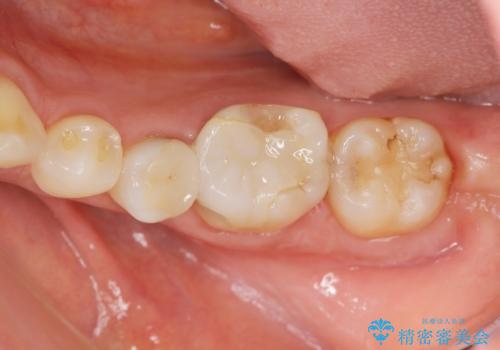

検診で判明した虫歯の再発

- 虫歯の全体的な検査を求めて来院されました。

X線検査を行なったところ、以前他院にて治療した白い詰め物の下に虫歯の再発を認めました。

詰め物を除去したのち、虫歯を丁寧に除去することで神経を保存しながらセラミッククラウンによる補綴治療を行うことができました。

外から見て白くきれいな修復が為されていたとしても、内部で虫歯が再発していることは多々あります。

違和感を感じたら早期にX線検査を行い、神経が保存できるうちに治療を行うことが重要です。